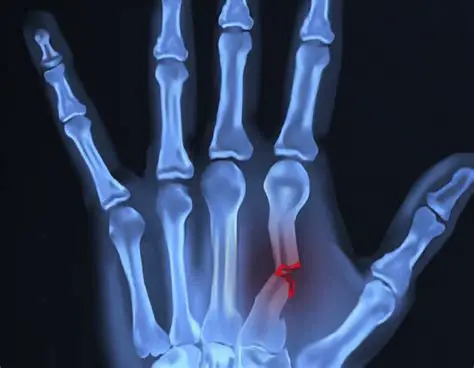

Hand Fractures